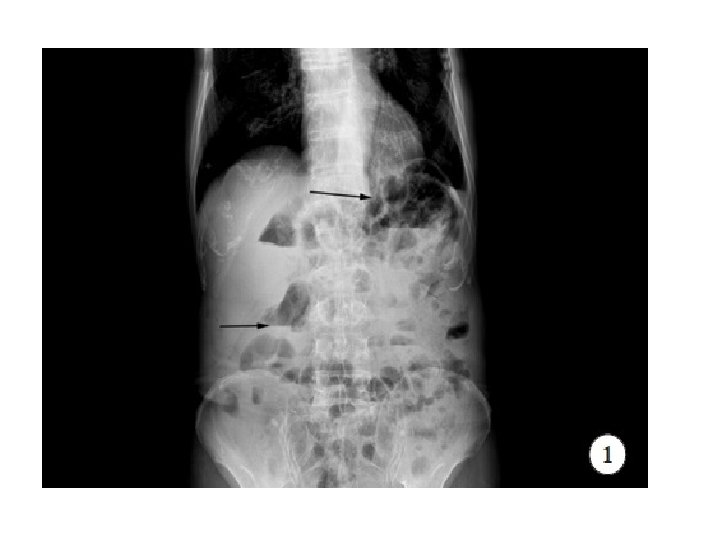

Intestinal Obstruction Supine Xray : Dilated/distended bowel loops Erect Xray : Multiple air-fluid levels Classifications: Based on Site: Small bowel or Large bowel Based on aetiopathology: Mechanical or Funtional • Based on onset : congenital or acquired • • •

Intestinal Obstruction • Congenital: anorectal malformation, intestinal atresia, congenital megacolon, congenital bands and adhesions. • Mechanical Obstruction: hernia, adhesion, volvulus, tuberculous stricture, malignancies, worm infestation, fecal impaction. • Functional Obstruction: electrolyte imbalance, spinal injuries, bowel surgeries.